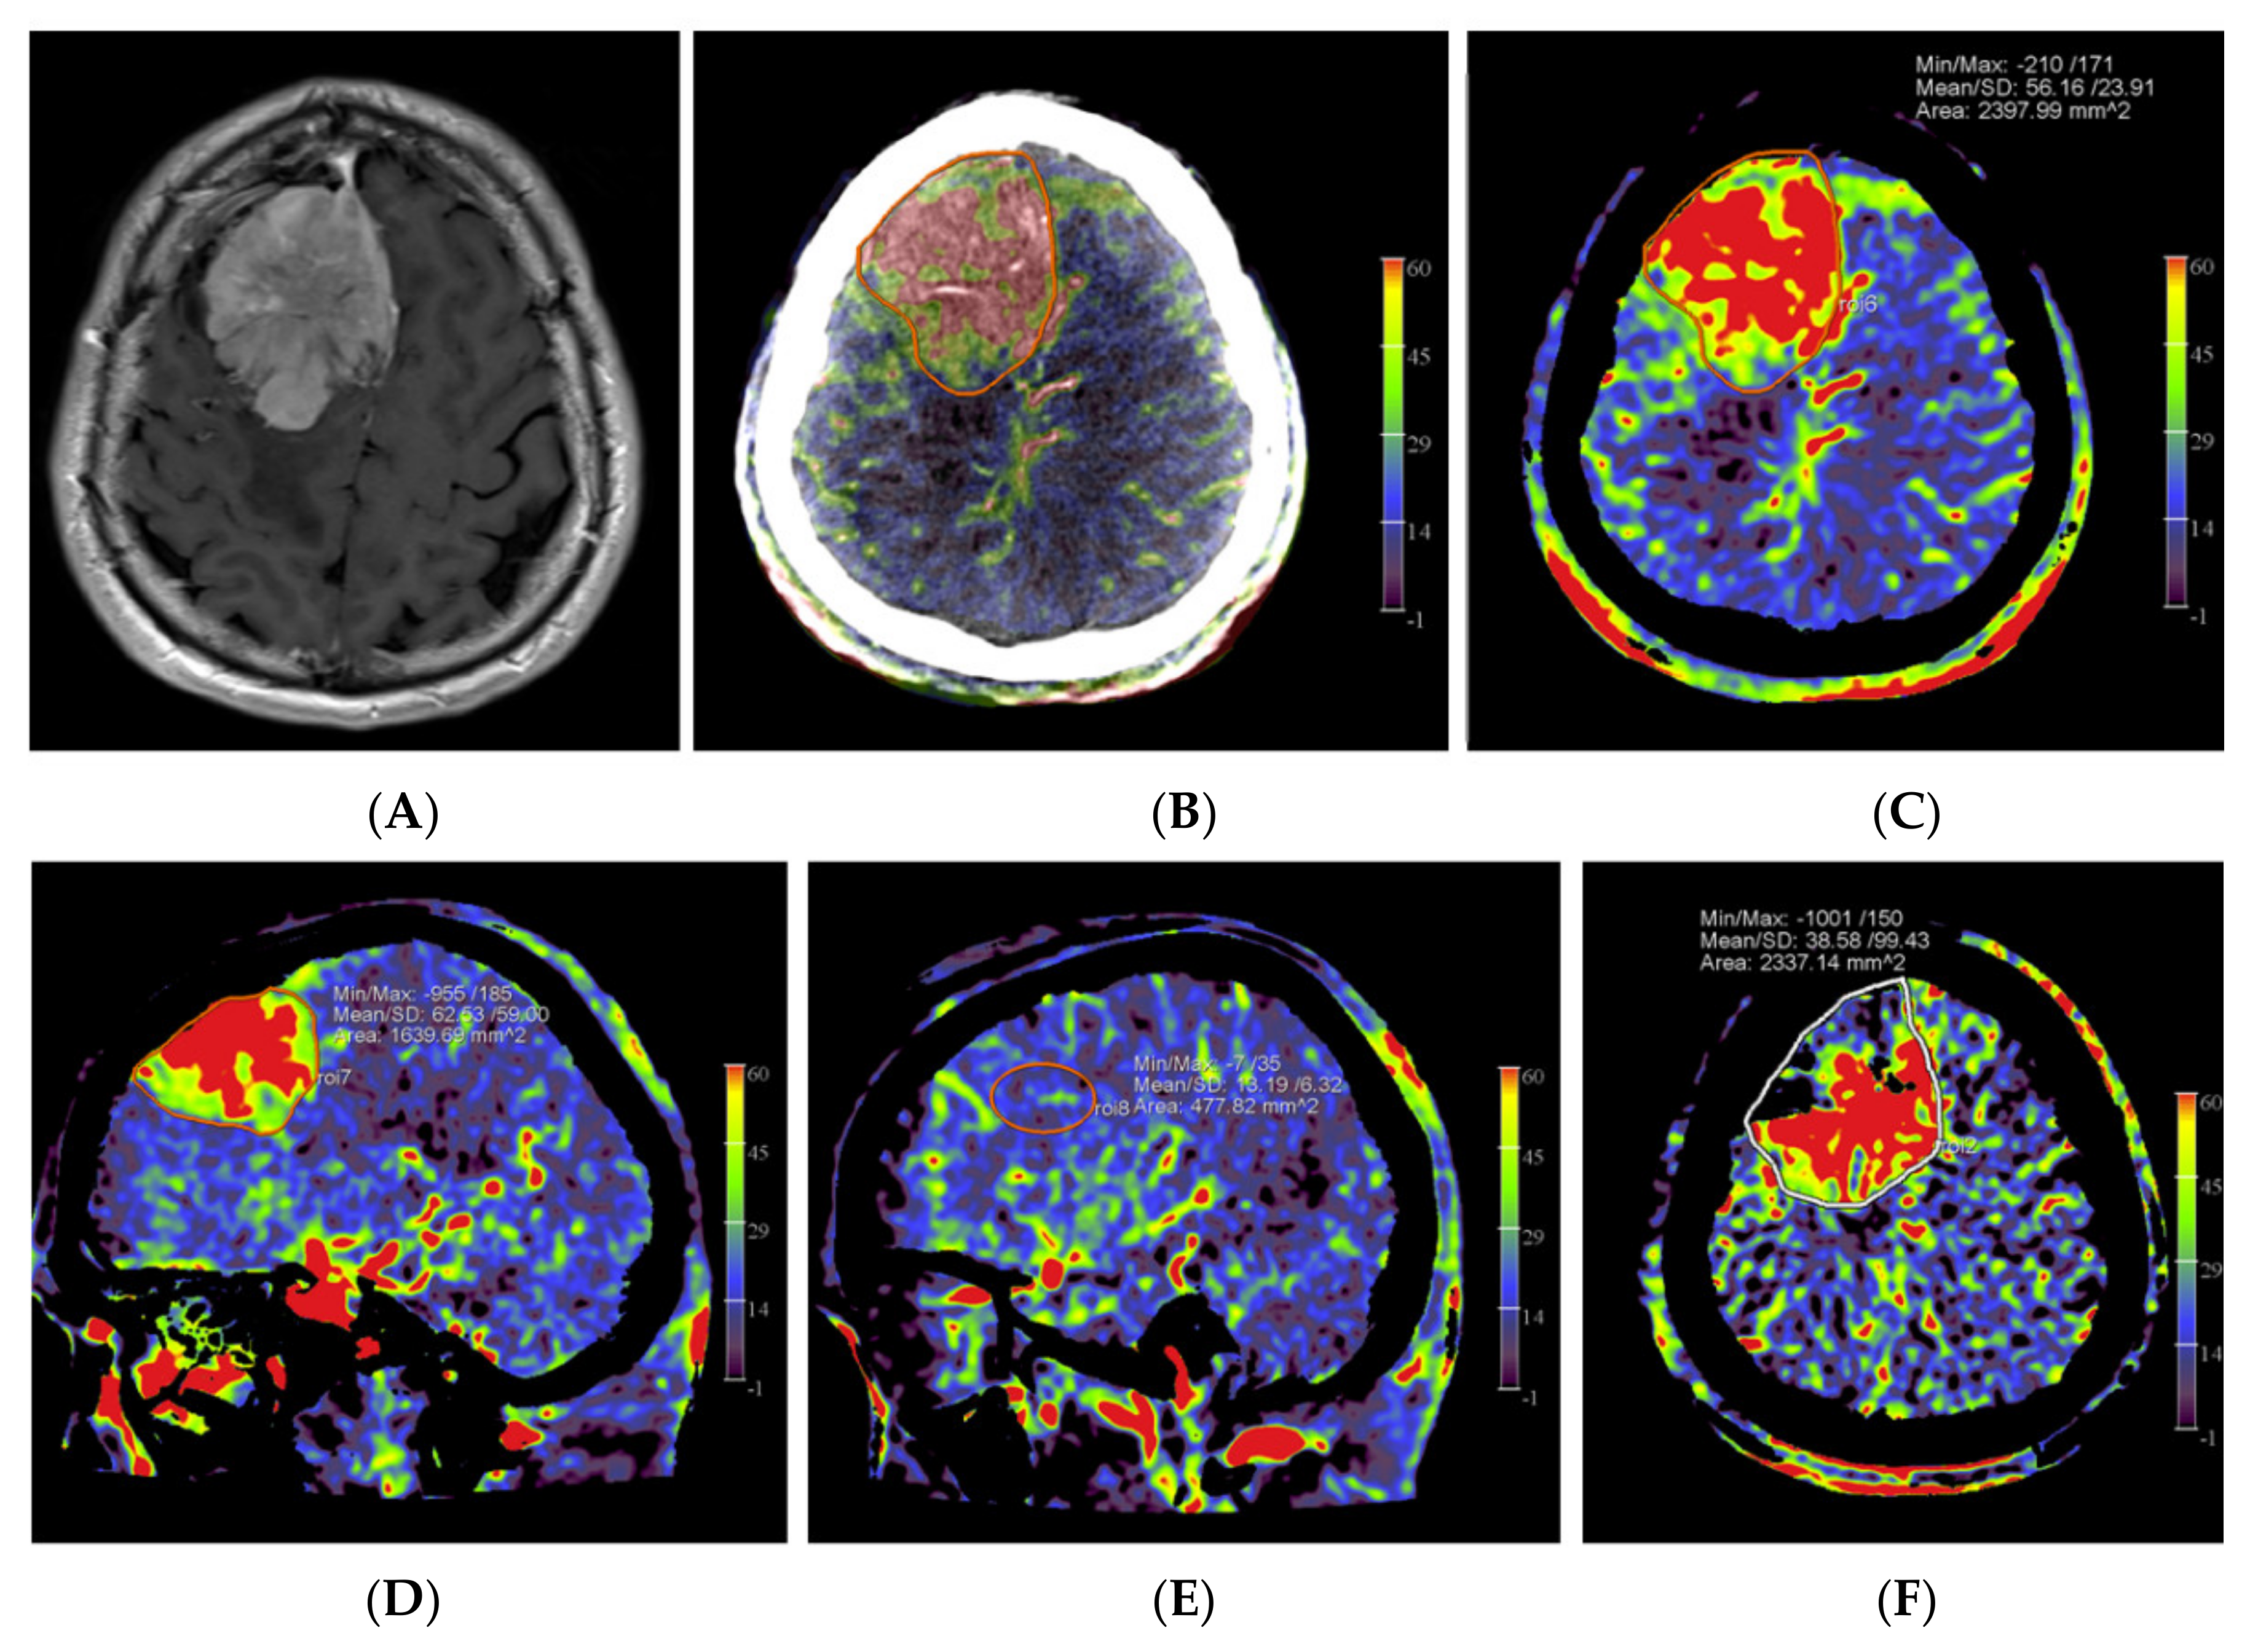

The angiographic PBV perfusion acquisitions were technically successful in all our patients. No adverse events occurred during the angiographic examinations or during or after the embolization procedures. In all patients, a mixed pial and dural vascular supply pattern was present. Figure 2 shows an example of the PBV images obtained after selective and aortic arch injections pre- and post-embolization, respectively.

Figure 2.

Imaging of a patient with a right-sided perisylvian meningioma. (A) Axial post-contrast T1-weighted MRI image of patient no. 4 shows the presence of an enhancing, extra-axially located tumor in the right perisylvian area. (B) Pre-embolization axial PBV reformation obtained after selective right external carotid artery injection and (C) after aortic root contrast injection shows a hypervascular tumor. In consultation with the operating neurosurgeon, a pre-operative embolization was performed. (D) Post-embolization axial reformation of whole brain PBV scan shows devascularization of the portion supplied by the dural feeder.